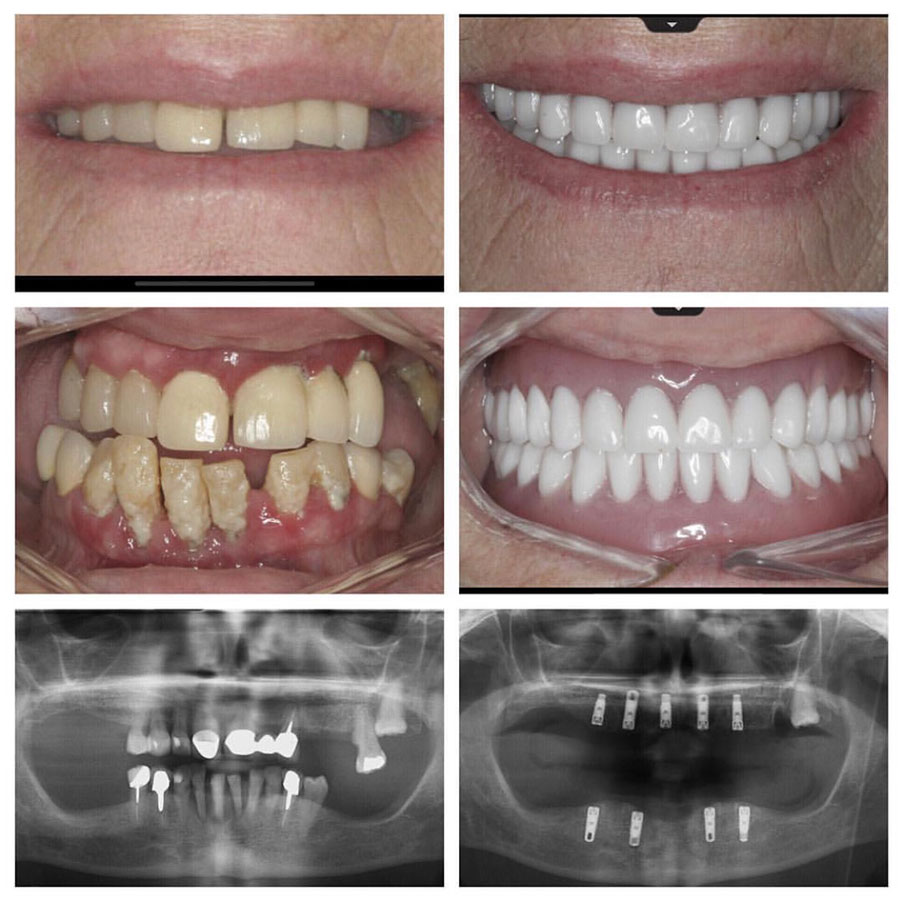

📸 Rezultati naših pacientov

Pred / po primeri

Nadomestitev manjkajočega zoba – naravni videz in funkcija

Obnova nasmeha po izgubi več zob – brez proteze

Popolna estetska prenova z implantati Straumann®